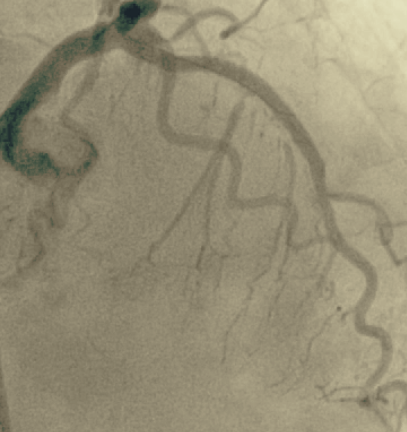

Verschlossenes Gefäß

Die wichtigste Therapie der koronaren Herzerkrankung besteht in der Aufweitung verengter Herzkranzgefäße (Ballonangioplastie/PTCA) und der Implantation von Gefäßstützen (Stents). Hierbei kommen zur bestmöglichen Versorgung unserer Patienten medikamentenbeschichtete Stents zum Einsatz. Besonders schwer verkalkte Herzkranzgefäße können auch mit einem kleinen Bohrkopf wieder erweitert werden (Rotablation).

Ein besonderer Schwerpunkt in unserer Klinik liegt auf der Versorgung komplexer Mehrgefäßerkrankungen, einschließlich Hauptstamminterventionen. Darüber hinaus werden aber auch chronisch verschlossenen Gefäße (CTO) rekanalisiert. Auf diese Weise können teilweise Bypass-Operationen vermieden werden.